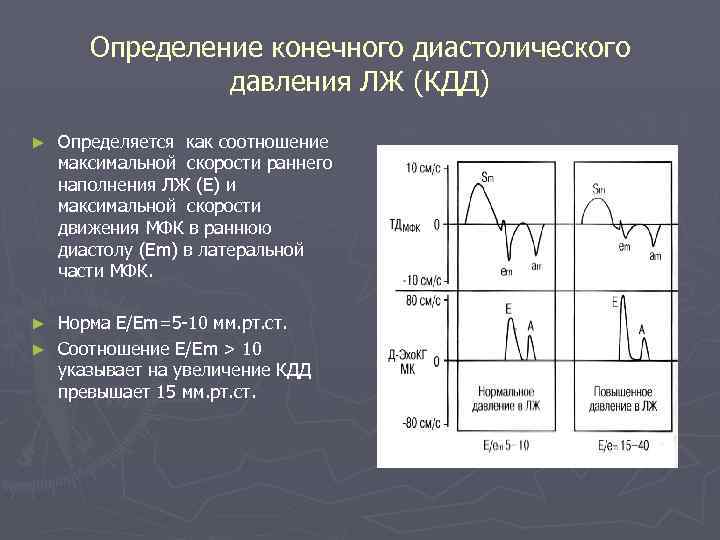

Определение конечного диастолического давления ЛЖ (КДД) ► Определяется как соотношение максимальной скорости раннего наполнения ЛЖ (Е) и максимальной скорости движения МФК в раннюю диастолу (Еm) в латеральной части МФК. Норма Е/Еm=5 -10 мм. рт. ст. ► Соотношение Е/Еm > 10 указывает на увеличение КДД превышает 15 мм. рт. ст. ►